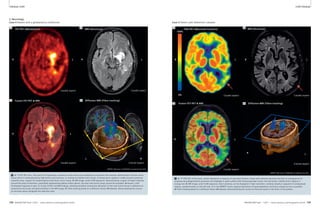

Figure 5 illustrates the potential value

of 7T scanning for a complementary

evaluation of proteoglycan content, and

therefore of cartilage function. These

images represent various slices through

3D volumetric sodium concentration

maps encompassing the whole knee in

a healthy subject as compared with a

patient with osteoarthritis (OA). The

enhanced SNR available at 7T enabled

whole-knee acquisitions at 2 mm isotro-pic

resolution in less than 15 minutes.

Such acquisitions would not be possible

at lower field strengths, given inherently

low MR sensitivity to sodium nuclei.

Through appropriate calibration, sodium

images were converted into quantitative

Healthy subject (average [Na] ~ 240-280 mM in 5 healthy subjects)

5B 5C 5D

Patient with OA (average [Na] ~ 180-240 mM in 5 patients)

5A

sodium concentrations, which may be

seen to be generally decreased in the

osteoarthritic as compared with the

healthy knee cartilage. Indeed, the aver-age

sodium concentration across the

knee cartilage in 5 patients with OA was

noticeably lower than that in a group of

5 healthy controls. This change reflects a

loss of proteoglycans, the removal of

whose net negative charge results in a

corresponding loss of positively-charged

sodium ions to preserve charge balance.

5E 5F 5G 5H

5 7T sodium imaging of cartilage in a healthy subject (top) and a patient with osteoarthritis (bottom). 7T field strength enabled whole-knee

3D volumetric sodium concentration maps at comparatively high resolution in less than 15 minutes. Note reductions in average sodium

concentration in arthritic versus healthy cartilage, both in the individual knees shown and in ensembles of 5 patients and 5 controls.

(Undersampled 3D radial pulse sequence, TR/TE 80/0.2 ms, 2.0 x 2.0 x 2.0 mm3, single-tuned quadrature sodium coil custom-designed in

collaboration with Rapid Biomedical, GmbH. Images courtesy of Ravi Regatte, Ph.D., Department of Radiology, NYULMC, USA.)